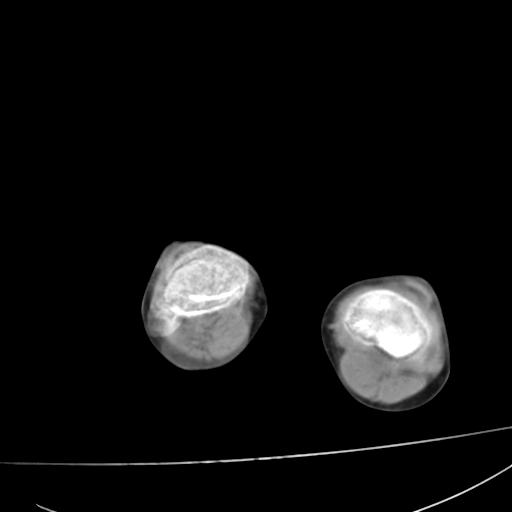

标题: PED0940:M12Y,左股骨下端酸痛畸形 [打印本页]

标题: PED0940:M12Y,左股骨下端酸痛畸形

12岁男孩,左膝关节肿痛8年,近月明显

内生骨软骨瘤?

血友性关节病?